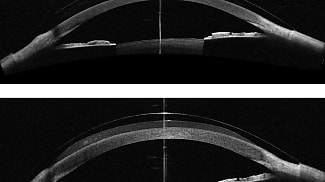

Specialized contact lens fitting continues to evolve, and today’s clinicians are increasingly confronted with unique scenarios that push the limits of traditional scleral lens design.

By Summer Hunt